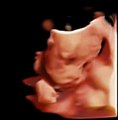

Chison training for 4D ultrasound, three dimensional image with movements. Learn how to get the best 4D image, and 4D scanning. <br />To buy Chison Q5 with 4D software and 4D probe visit: http://www.keebomed.com/collections/color-doppler-ultrasounds/products/chison-q5-color-doppler-ultrasound-1